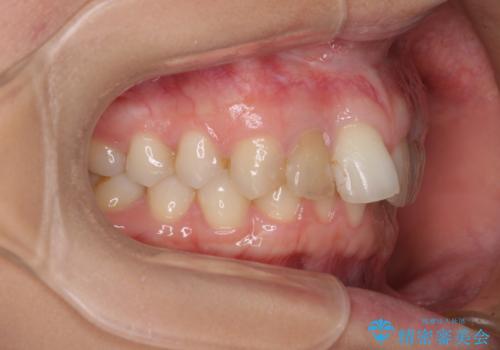

- 前歯の歯並びと神経を取って変色してしまった前歯を気にして来院された患者様です。

上下前歯の歯列不正はインビザラインにより整え、その後に、前歯2本をオールセラミッククラウンにて補綴治療することとしました。

下顎前歯が1本欠損しており、下顎歯列の大きさが本来よりも小さいため、上顎歯列とのバランスが悪く、深い咬み合わせになっていました。

上顎にIPRを多用して歯列の大きさを小さくするよう試みましたが、理想的な咬み合わせまでには改善させることはできませんでした。